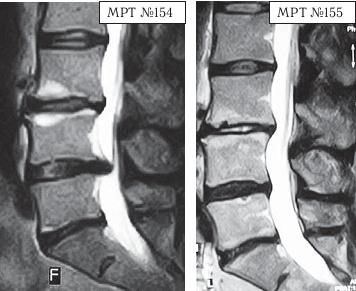

МРТ № 1

На магнитно-резонансной томографии (МРТ) № 1 — шейный отдел позвоночника, в относительно нормальном состоянии.

Шейный отдел позвоночника должен иметь нормально выраженный физиологический лордоз, не должно быть гиполордоза или гиперлордоза, а так же кифотических деформаций.

МРТ № 2

На МРТ № 2 — грудной отдел в состоянии «норма»

Грудной отдел должен иметь нормальную степень кифоза (угол кифоза по Stagnara формируется линией, параллельной замыкательным пластинкам ТIII и ТXI= 25°). Позвоночный канал на грудном уровне имеет округлую форму, что делает эпидуральное пространство узким почти по всей окружности дурального мешка (0,2–0,4 см), а на участке между TVI и ТIX он наиболее узок. Сагиттальный размер: ТIХI = 13–14 мм, ТXII = 15 мм. Поперечный диаметр: > 20–21 мм.

Высота межпозвонковых дисков: самая меньшая на уровне ТI, на уровне ТVIХI приблизительно 4–5 мм, наибольшая на уровне ТХIХII.

МРТ № 3

На МРТ № 3 — поясничный отдел позвоночника. (На данном «контрольном» снимке наблюдаются остаточные явления дегенеративно-дистрофического процесса в сегменте LV-SI после устранения методом вертеброревитологии секвестрированной грыжи межпозвонкового диска.)

В поясничном отделе форма позвоночного канала, создаваемая телом и дужками позвонка, вариабельна, но чаще она пятиугольная. В норме позвоночный канал в пояснично-крестцовом отделе сужен в переднезаднем диаметре на уровне LIII и LIV позвонков. Его диаметр каудально увеличивается, и поперечное сечение канала приобретает форму, близкую к треугольной, на уровне LV-SI. У женщин канал имеет тенденцию к расширению в нижней части крестцовой области. Сагиттальный диаметр значительно уменьшается от LI к LIII почти неизменен от LIII к LIV и увеличивается от LIV к LV. В норме переднезадний диаметр позвоночного канала в среднем равен 21 мм (15–25 мм).